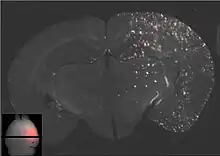

- Ultrasons focalisés avec des microbulles

Les ultrasons peuvent être focalisés sur n'importe quel domaine du cerveau. C'est ainsi que l'on peut ouvrir la barrière hémato-encéphalique sélectivement sur des régions délimitées du cerveau. Les médicaments administrés pénétreront alors sur la zone ainsi ciblée[138]. On peut suivre le ciblage des zones par une IRM simultanée : il suffit d'administrer un produit de contraste IRM, comme du gadolinium convenablement chélaté, qui pénètre dans le cerveau à travers les parties de la barrière hémato-encéphalique ouvertes. Ces parties deviennent alors visibles en IRM. Les produits de contraste ne sont pas en mesure de franchir la barrière aux endroits où elle n'est pas ouverte.

Le mécanisme de l'ouverture de la barrière hémato-encéphalique par utilisation d'ultrasons focalisés et de microbulles n'est pas encore complètement élucidé. L'interaction entre les ultrasons et les microbulles y joue un grand rôle, et conduit in vivo à toute une série d'effets biologiques[143]. Il semble qu'un grand rôle est joué par les forces de cisaillement créées par les microcourants. Ces microcourants eux-mêmes proviennent des oscillations des microbulles dans le champ d'ultrasons[143]. On sait déjà que les endothéliums peuvent réagir dynamiquement aux forces de cisaillement, et que ces forces de cisaillement sont une grandeur critique pour l'homéostasie[144]. Les vues en microscopie électronique des capillaires d'animaux ainsi traités présentent des signes aussi bien de transport transcellulaire que paracellulaire de molécules marqueurs (péroxydase du raifort). Le transport transcellulaire est la transcytose, tandis que le transport paracellulaire est initié par un processus complexe de désintégration, qui fait perdre leur fonction aux jonctions serrées[145].

La barrière hémato-encéphalique ainsi ouverte est perméable pour les médicaments de chimiothérapie de faible masse moléculaire, comme la doxorubicine[146], et des anticorps come le Trastuzumab[147],[148],[149]. La faisabilité de principe du transport dans le cerveau a été démontrée avec cette méthode même pour des gènes sur des modèles animaux[150],[142]. Le procédé d'ouverture de la barrière hémato-encéphalique par ultrasons et injection simultanée de microbulles en est encore à ses débuts. Jusqu'à présent, il n'a été testé que sur des animaux. L'expérience conduit à penser qu'il se passera encore de nombreuses années jusqu’à ce qu'il soit autorisé sur l’homme.